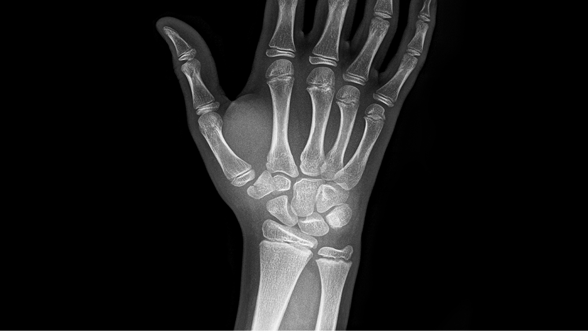

척골 신경 증후군

손목관절의 척측(새끼손가락 쪽)에 과도한 하중이 반복적으로 가해질 때

통증, 붓기, 관절 운동 제한, 근력감소 증상이 나타나게 되는 퇴행성 질환입니다.

비수술 치료 : 고정치료(보조기), 주사치료, 도수치료